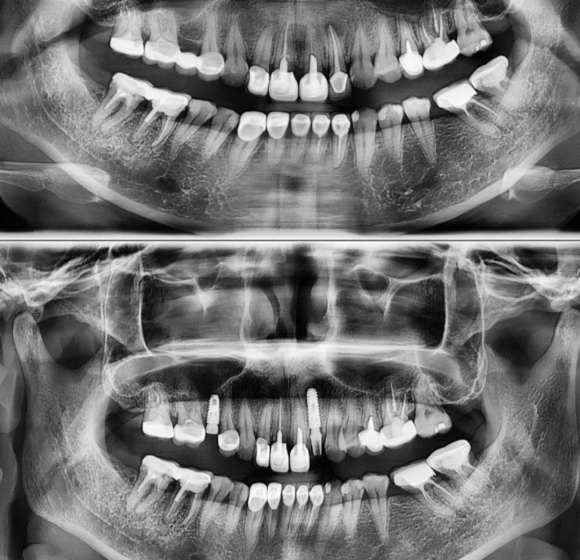

상기 60대 여환자 치아를 발치하고 브릿지를 사용한지 오래 되었으며

어금니에 힘이 받지 않아서 임플란트를 꼭 원하셔서 하시게된 케이스 입니다.

건 양쪽 치아 크라운은 건전했기 때문에 살리기 위해 커팅을 진행하였으며

치아가 발치된지 오래된 상태로 해당부위 뼈가 많이 얇아지고 약해진 상태여서

덴샤버를 이용해 드릴과 뼈의 densification을 동시에 얻고

성공적인 임플란트 수술을 완성하게 되었습니다.